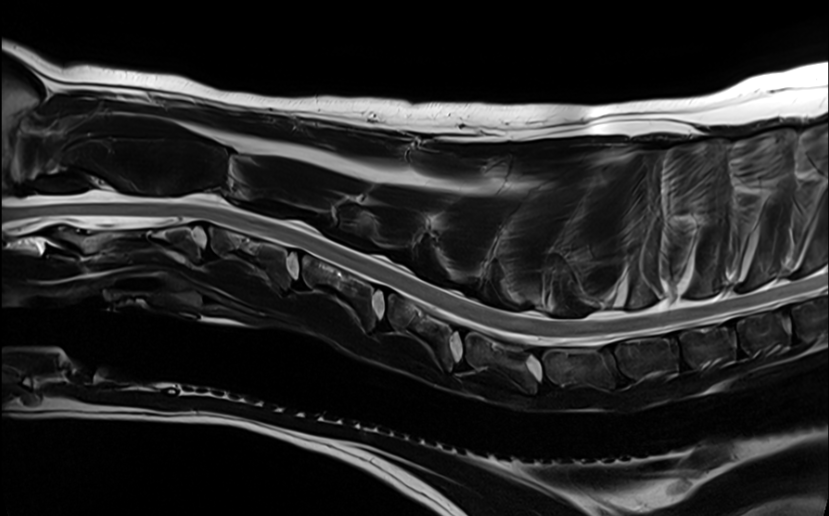

MRI

We have recently undergone software upgrades to our 1.5T MRI facility resulting in even greater image detail and reduced scan times, allowing reduced anaesthesia times for our patients. The quality of images of structures such as the brain, eye, spinal cord, and musculoskeletal system is exceptional.

We accept appropriate outpatient referrals for stable patients and perform a wide range of studies for our medicine and surgery service inpatients. For more information about our MRI service, you can call or email the Radiology department and speak with our MIT, charge nurse or radiologists.